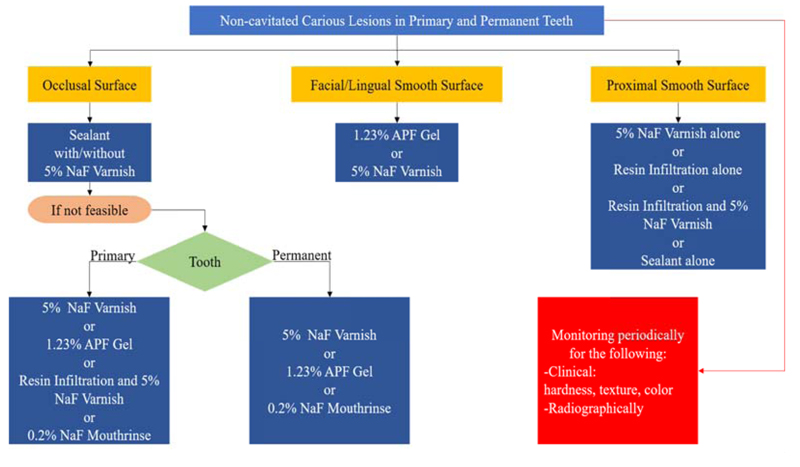

The American Dental Association Council assembled an expert panel to establish a systematic review and make evidence-based clinical recommendations to arrest or reverse non-cavitated and cavitated dental carious lesions using nonrestorative treatment approaches in both children and adult patients [50]. The investigators carried out systematic research in different databases to examine the randomized controlled trials that were carried out on nonrestorative treatments of non-cavitated and cavitated dental carious lesions. The expert panel assessed the certainty in the evidence using the Grading of Recommendations Assessment, Development and Evaluation (GRADE) approach.This approach was developed to assess the certainty and the quality of evidence by a widely representative group of international guideline developers to create a clear separation between the quality of evidence and strength of recommendations,as well as to evaluate the importance of outcomes of alternative management strategies. Accordingly, the process of extracting recommendations from the evidence is transparent and clear, leading to the interpretation of strong versus weak recommendations for clinicians, patients, and policymakers [70]. Based on that, Slayton et al. in 2018 formulated eleven clinical recommendations, each specific to lesion type, tooth surface, and dentition (Fig. 4). Therefore, regarding non-cavitated lesions, they provided recommendations for sealants, 5% sodium fluoride varnish, 1.23% acidulated phosphate fluoride gel, and 5,000 parts per million fluoride (1.1% sodium fluoride) toothpaste or gel. The authors recommended non-invasive treatments for non-cavitated carious lesions because these approaches have shown to be effective in arresting or reversing carious lesions [50].

Abbreviations: NaF: Sodium Fluoride Varnish, APF: Acidulated Phosphate Fluoride

Consideration of the comprehensive planning and management of the carious lesions, whether cavitated or not, is the most reliable way to stop caries activity. Moreover, the visual-tactile and radiographic detection of non-cavitated carious lesions can be complemented by the use of advanced, non-invasive detection tools like DIAGNOdent, fiber-optic transillumination, quantitative light-induced fluorescence, and DIAGNOcam. Accordingly, non-cavitated carious lesions can be arrested by several non-invasive techniques, which are preferred over invasive restorative options.In both primary and permanent teeth, clinicians can use sealants in addition to fluoride varnish on occlusal surfaces, fluoride varnish or resin infiltration on proximal surfaces, andresin infiltration, a fluoride gel, or varnish alone on facial or lingual surfaces to manage non-cavitated carious lesions.